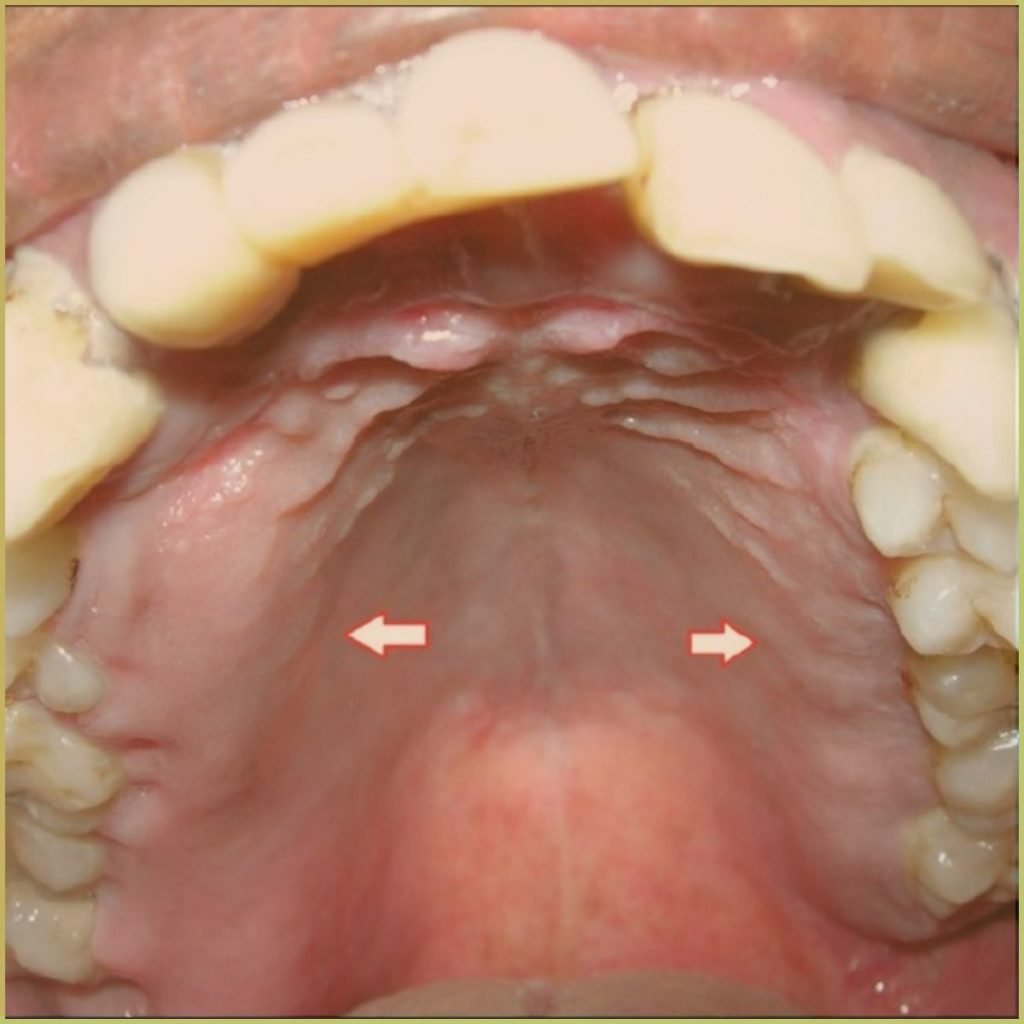

PAGET'S DISEASE

Paget’s Disease (osteitis deformans) is a condition characterized by aberrant cellular remodeling and deformity of one or more bones. Pathological structural changes cause the bone to weaken, which may result in deformity, pain, fracture or arthritis of associated joints. The exact cause is unknown, but possible etiological factors include viral exposure or autoimmune-mediated vascular disorders. The common clinical presentation includes:

- Pain, often presenting as deep aching pain in affected bones.

- Bones are usually affected bilaterally and symmetrically.

- Bony enlargement is common.

- The mandible and maxilla are commonly affected.

- Associated neurologic complications including vertigo, headache, auditory and/or visual disturbances, and facial paresthesia.

- Dental patients often complain of ill-fitting prostheses or slow separation of teeth.

- Possible radiographic changes include multiple lytic lesions, patchy “cotton wool” like radiopaque pattern, “drumstick” hypercementosis, and obliterated periodontal ligament spaces.

Patients usually present with increased serum alkaline phosphatase, urinary calcium, and hydroxyproline levels. Serum calcium and phosphate levels are normal. Diagnosis is based on the lesion history, clinical and radiographic presentation, and microscopic findings, which may include:

- Early phase – elevated osteoclastic resorption, fibrous tissue replacement of bone, and prominent blood vessels.

- Late phase – elevated osteoblastic function, which results in dense bony deposition with numerous reversal lines.

Your differential diagnosis should include:

- Osteosarcoma.

- Fibrous dysplasia.

- Acromegaly.